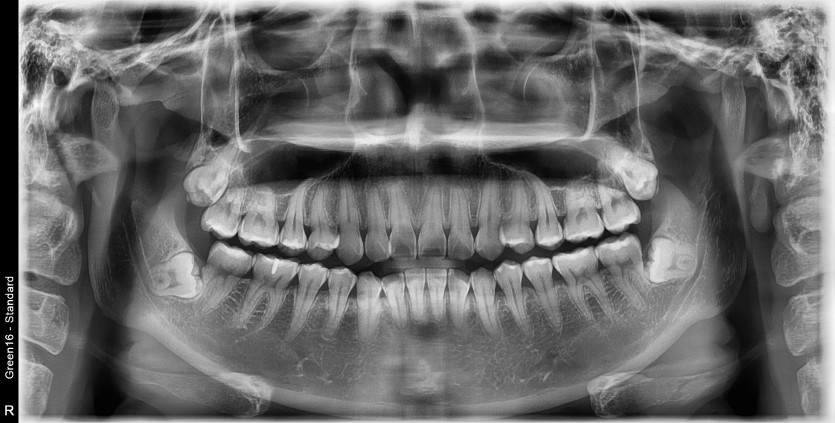

#18,48 사랑니 발치

구강외과 전문의가 당일발치했습니다.